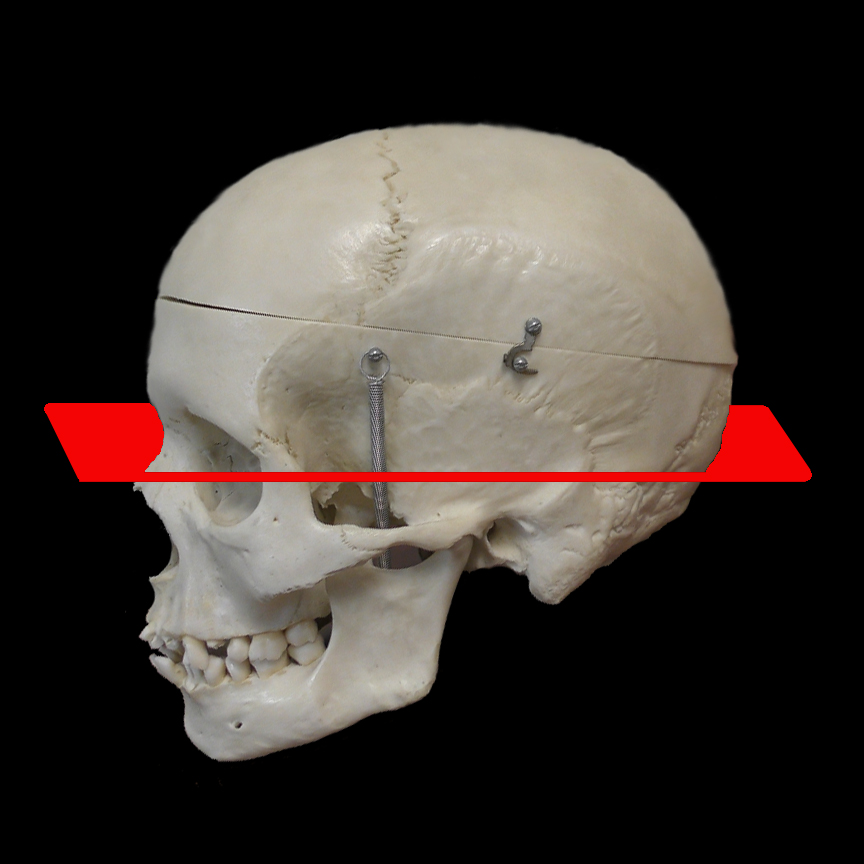

CT sinus scans are obtained in basically two different orientations: axial and coronal. Axial is if you slice the head in the horizontal plane whereas the coronal plane is in the vertical direction.

![]() |

| Axial |